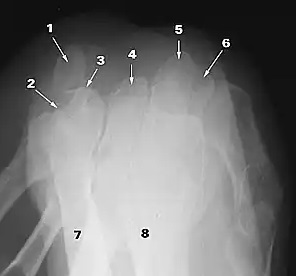

What does 2 indicate?

triquetrum

What does 3 indicate?

hook of hamate

What does 4 indicate?

capitate

What does 5 indicate?

scaphoid

What does 6 indicate?

trapezium

What does 7 indicate?

ulna

What does 8 indicate?

radius

What does 1 indicate?

pisiform